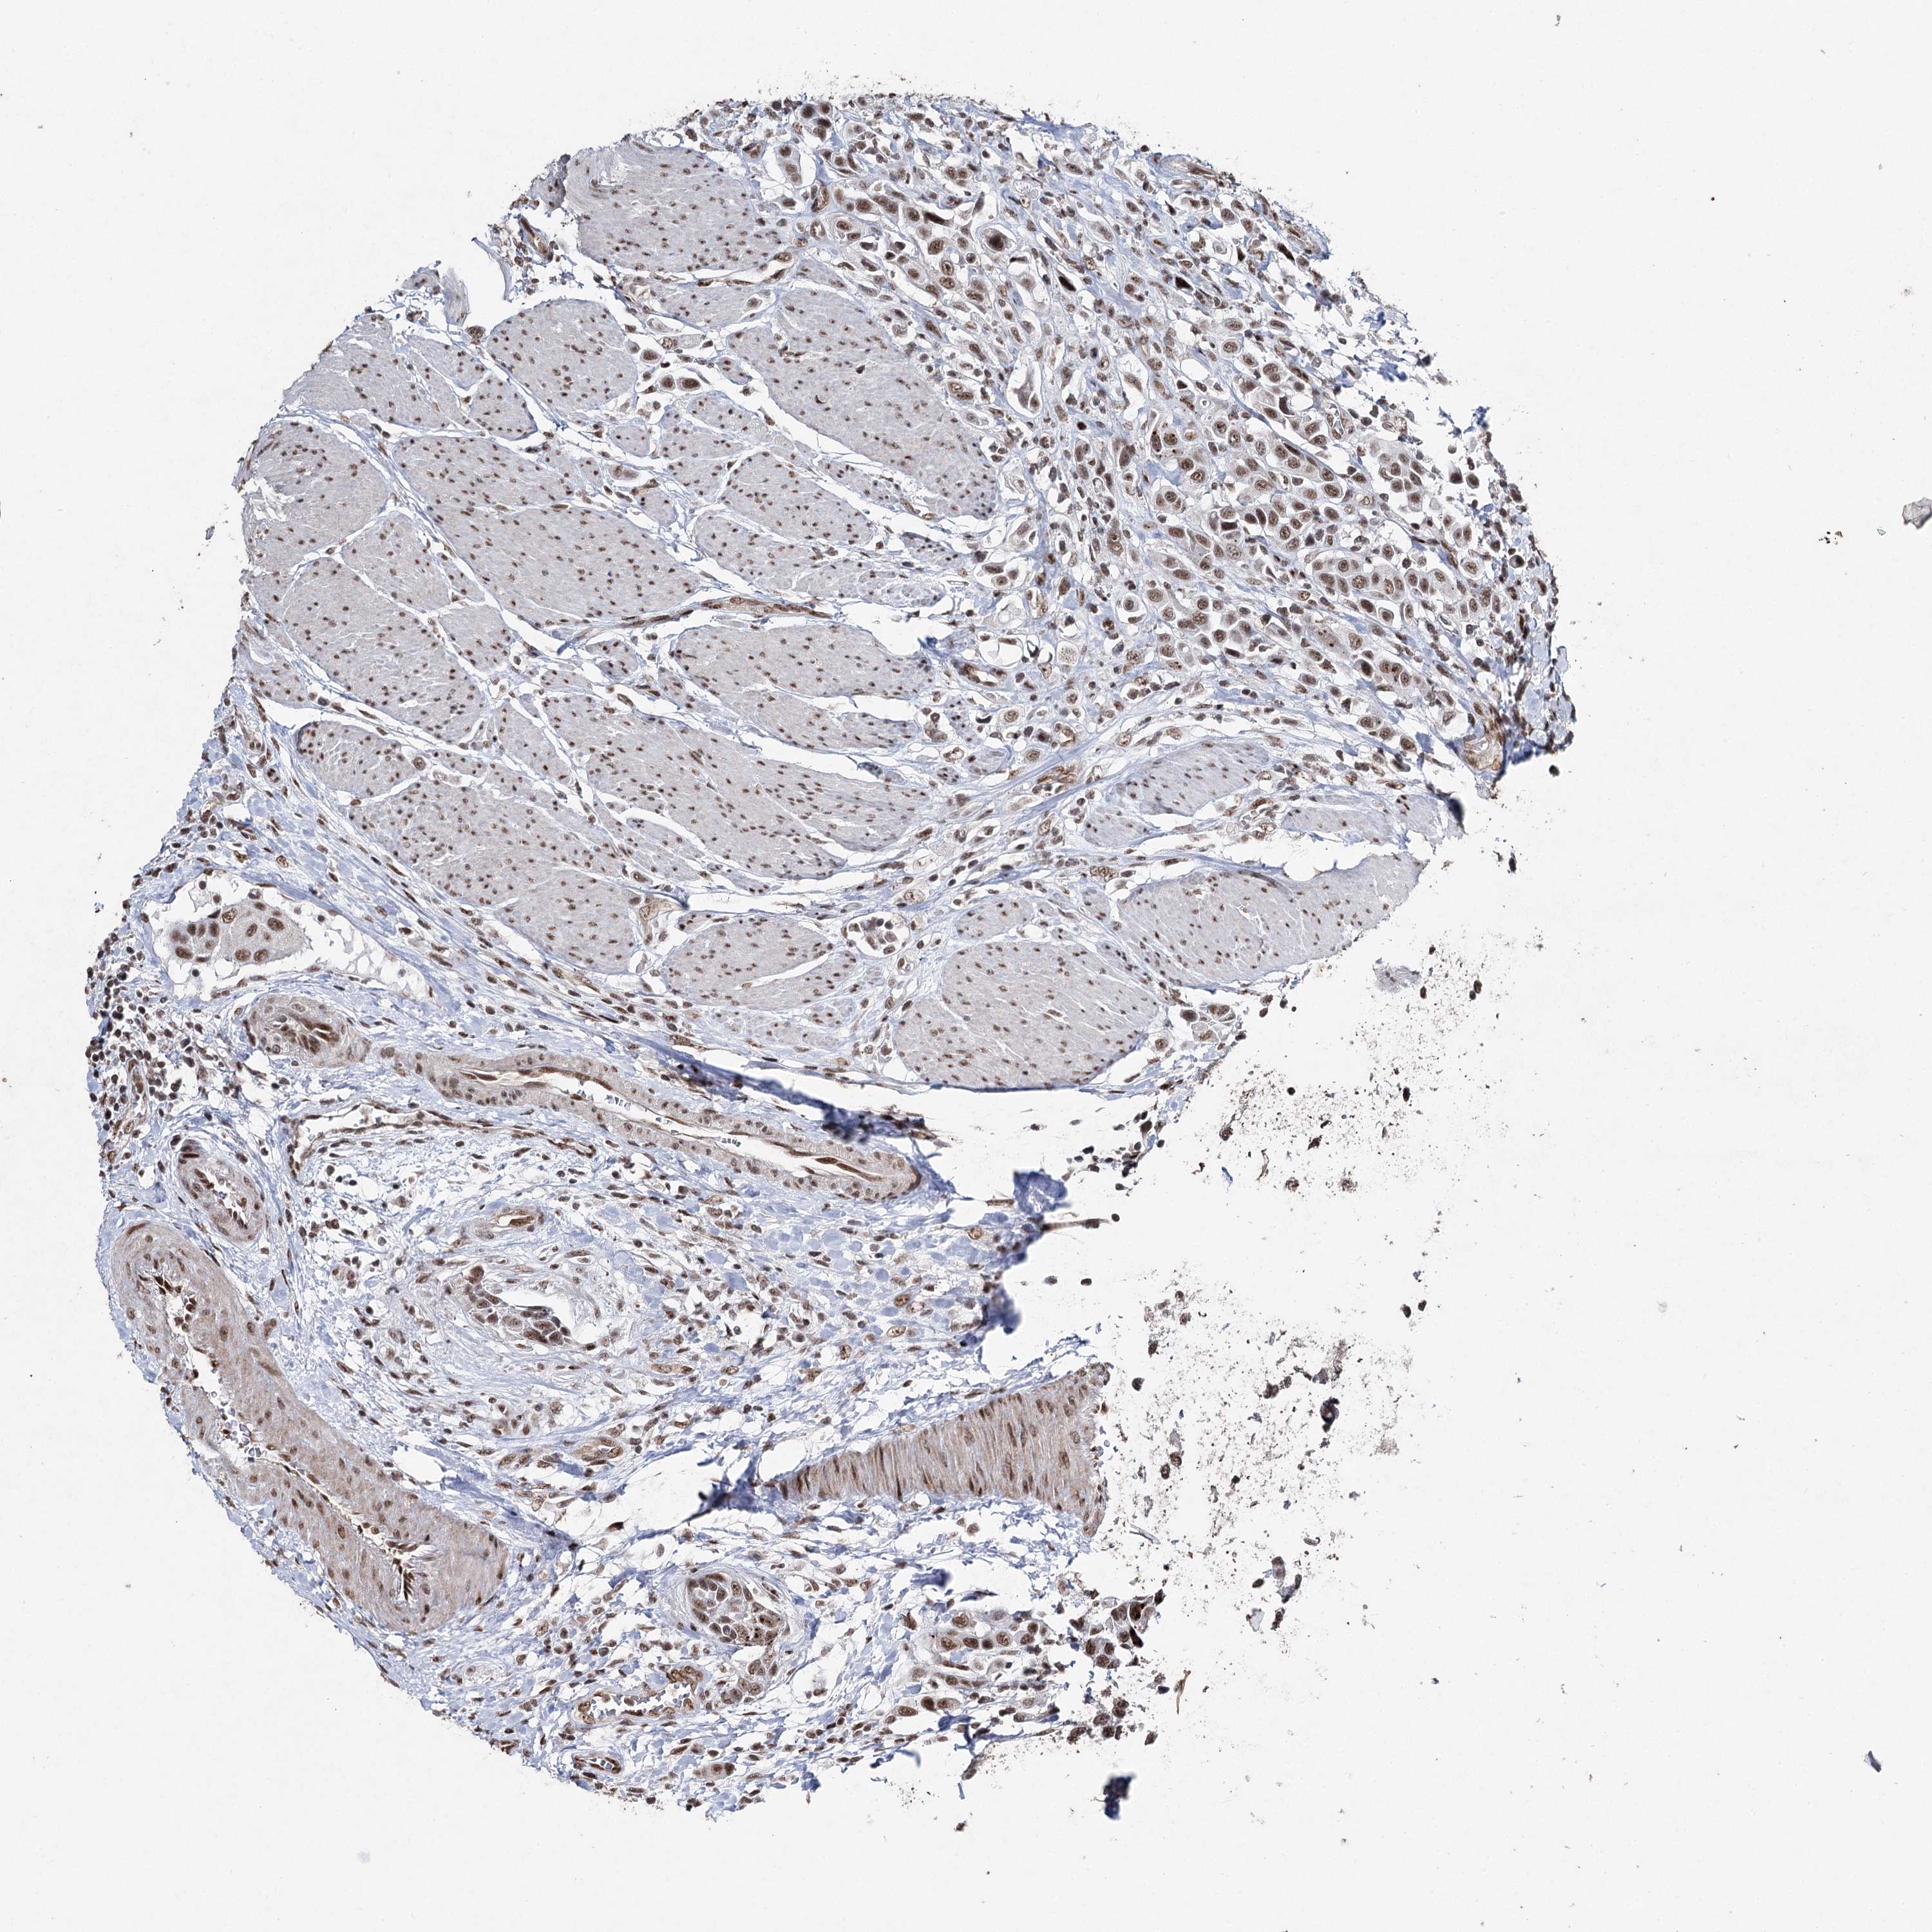

UROTHELIAL CANCER - Protein expressioni

A mouse-over function shows sample information and annotation data. Click on an image to view it in a full screen mode. Samples can be filtered based on level of antibody staining by selecting one or several of the following categories: high, medium, low and not detected. The assay and annotation is described here.

Antibody stainingi

Antibody staining in the annotated cell types in the current human tissue is reported as not detected, low, medium, or high, based on conventional immunohistochemistry profiling in selected tissues. This score is based on the combination of the staining intensity and fraction of stained cells.

Each image is clickable and will lead to virtual microscopy that enables deeper exploration of all samples and also displays staining intensity scores, fraction scores and subcellular localization as well as patient and tissue information for each sample.

Antibody HPA001032

Antibody HPA027214

Antibody CAB037024

Staining

High

Medium

Low

Not detected

Intensity

Strong

Moderate

Weak

Negative

Quantity

>75%

75%-25%

<25%

None

Location

Nuclear

Cytoplasmic/membranous

Cytoplasmic/membranous,nuclear

Urothelial carcinoma, High grade

Urothelial carcinoma, Low grade

Urothelial carcinoma, NOS